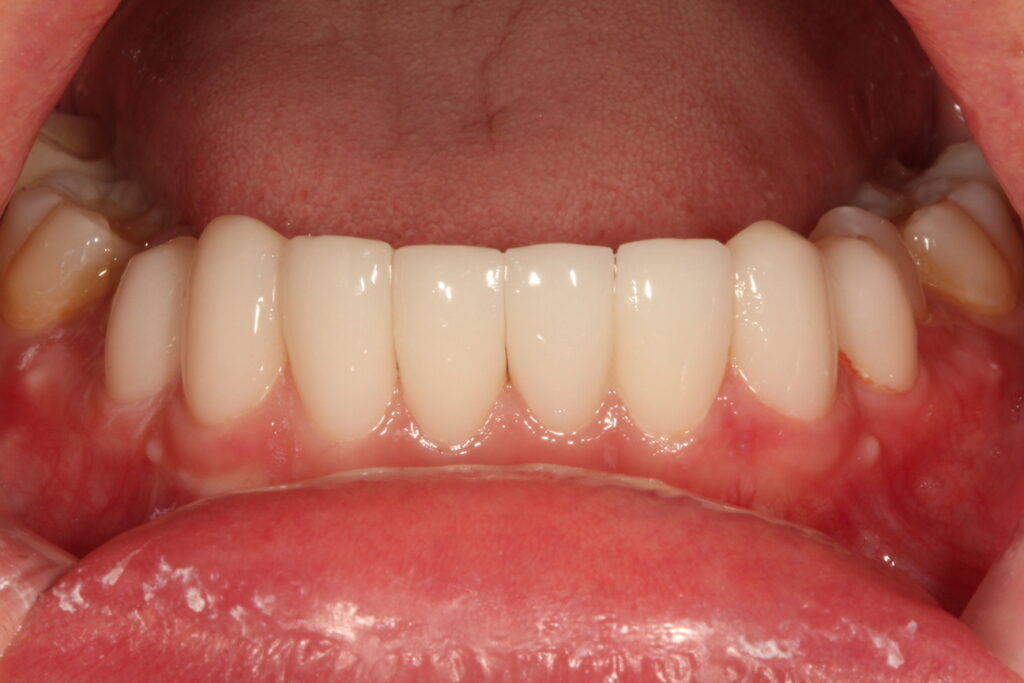

그래서 한 개의 치아는 예방적 신경치료후 올세라믹크라운으로 치료합니다. 나머지 치아들은 비교적 고른 편이라 라미네이트가 잘 붙게 하기 위한 정도의 다듬기만 해 주거나 삭제를 하지 않습니다.

치료후 상태

우선 치료기간이 단 하루면 가능하기 때문에 교정보다 유리합니다. 그리고 교정후 다시 치아가 틀어질까바 보정을 하는 번거로움이 없습니다. 주변의 치아를 같이 라미네이트로 치료할 경우 치아미백 효과까지 볼 수 있습니다.